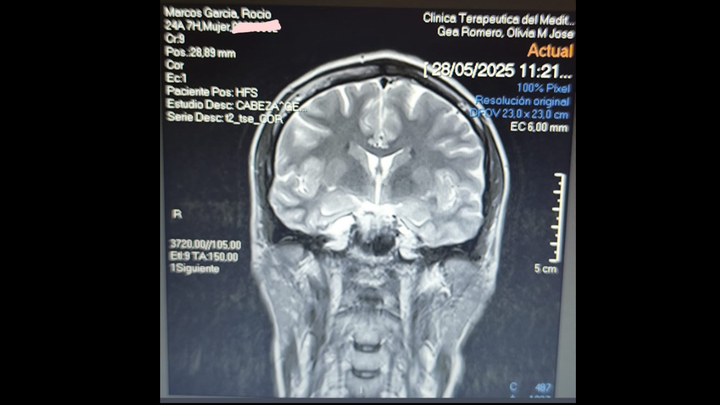

Hola, me llamo Rocio y hace poco me dijeron que tenía un quiste aracnoideo cerebral, hago esta recaudación de fondos ya que al trabajar en el ejército no puedo ir por lo público, he conseguido que me operen a principios de julio pero la operación tiene un precio bastante costoso, por lo cual toda ayuda que me deis os la agradecería muchísimo, muchas gracias a todos de antemano.